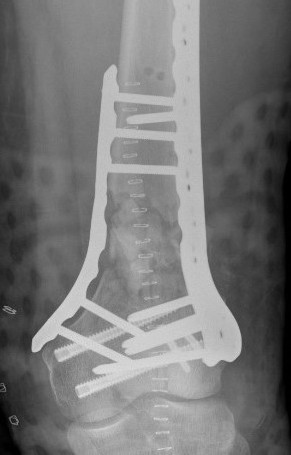

![]() |

Type C: Complete articular

Xray / CT

Options

Dual Plate

Plate + Retrograde nail

Distal femur replacement

Indications

Significant comminution

Loss of medial cortical buttress